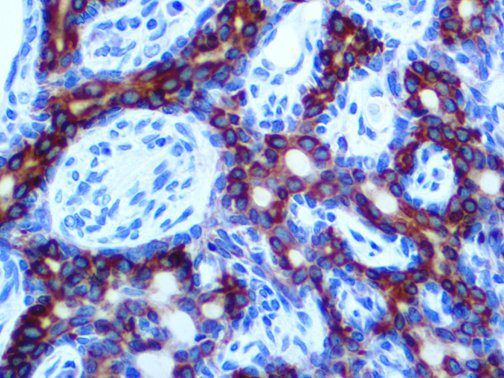

The first cytokines released are interleukin 1β (IL-1β) and tumor necrosis factor-α (TNF-α), which attract a variety of circulating white blood cells (WBCs) to the infection site, including neutrophils, monocytes, macrophages, and natural killer (NK) cells. This response, along with the antipathogenic chemicals released by these cells (i.e., complement), comprise the innate immune response. These cells directly attack the invading pathogen and also release additional cytokines, chief among them interleukin-1 and 6 (IL-6). IL-6 is essential for invoking the adaptive immune response, which calls T-cells, B-cells, and T helper (Th) cells to the infection site. IL-6 also stimulates further recruitment, proliferation and activation of macrophages.

It is the ICU physician who is most likely to witness one of the deadliest manifestations of the abnormal immunological response, the cytokine storm syndrome (CSS). This response is also referred to by some as the cytokine release syndrome (CRS). CSS is characterized by continuous activation and expansion of macrophage and lymphocyte populations, which secrete large amounts of cytokines, causing the cytokine storm. This massive cytokine release is akin to hemophagocytic lymphohistiocytosis (HLH) disease, a syndrome characterized by initial unchecked and persistent activation of cytotoxic T lymphocytes and NK cells.